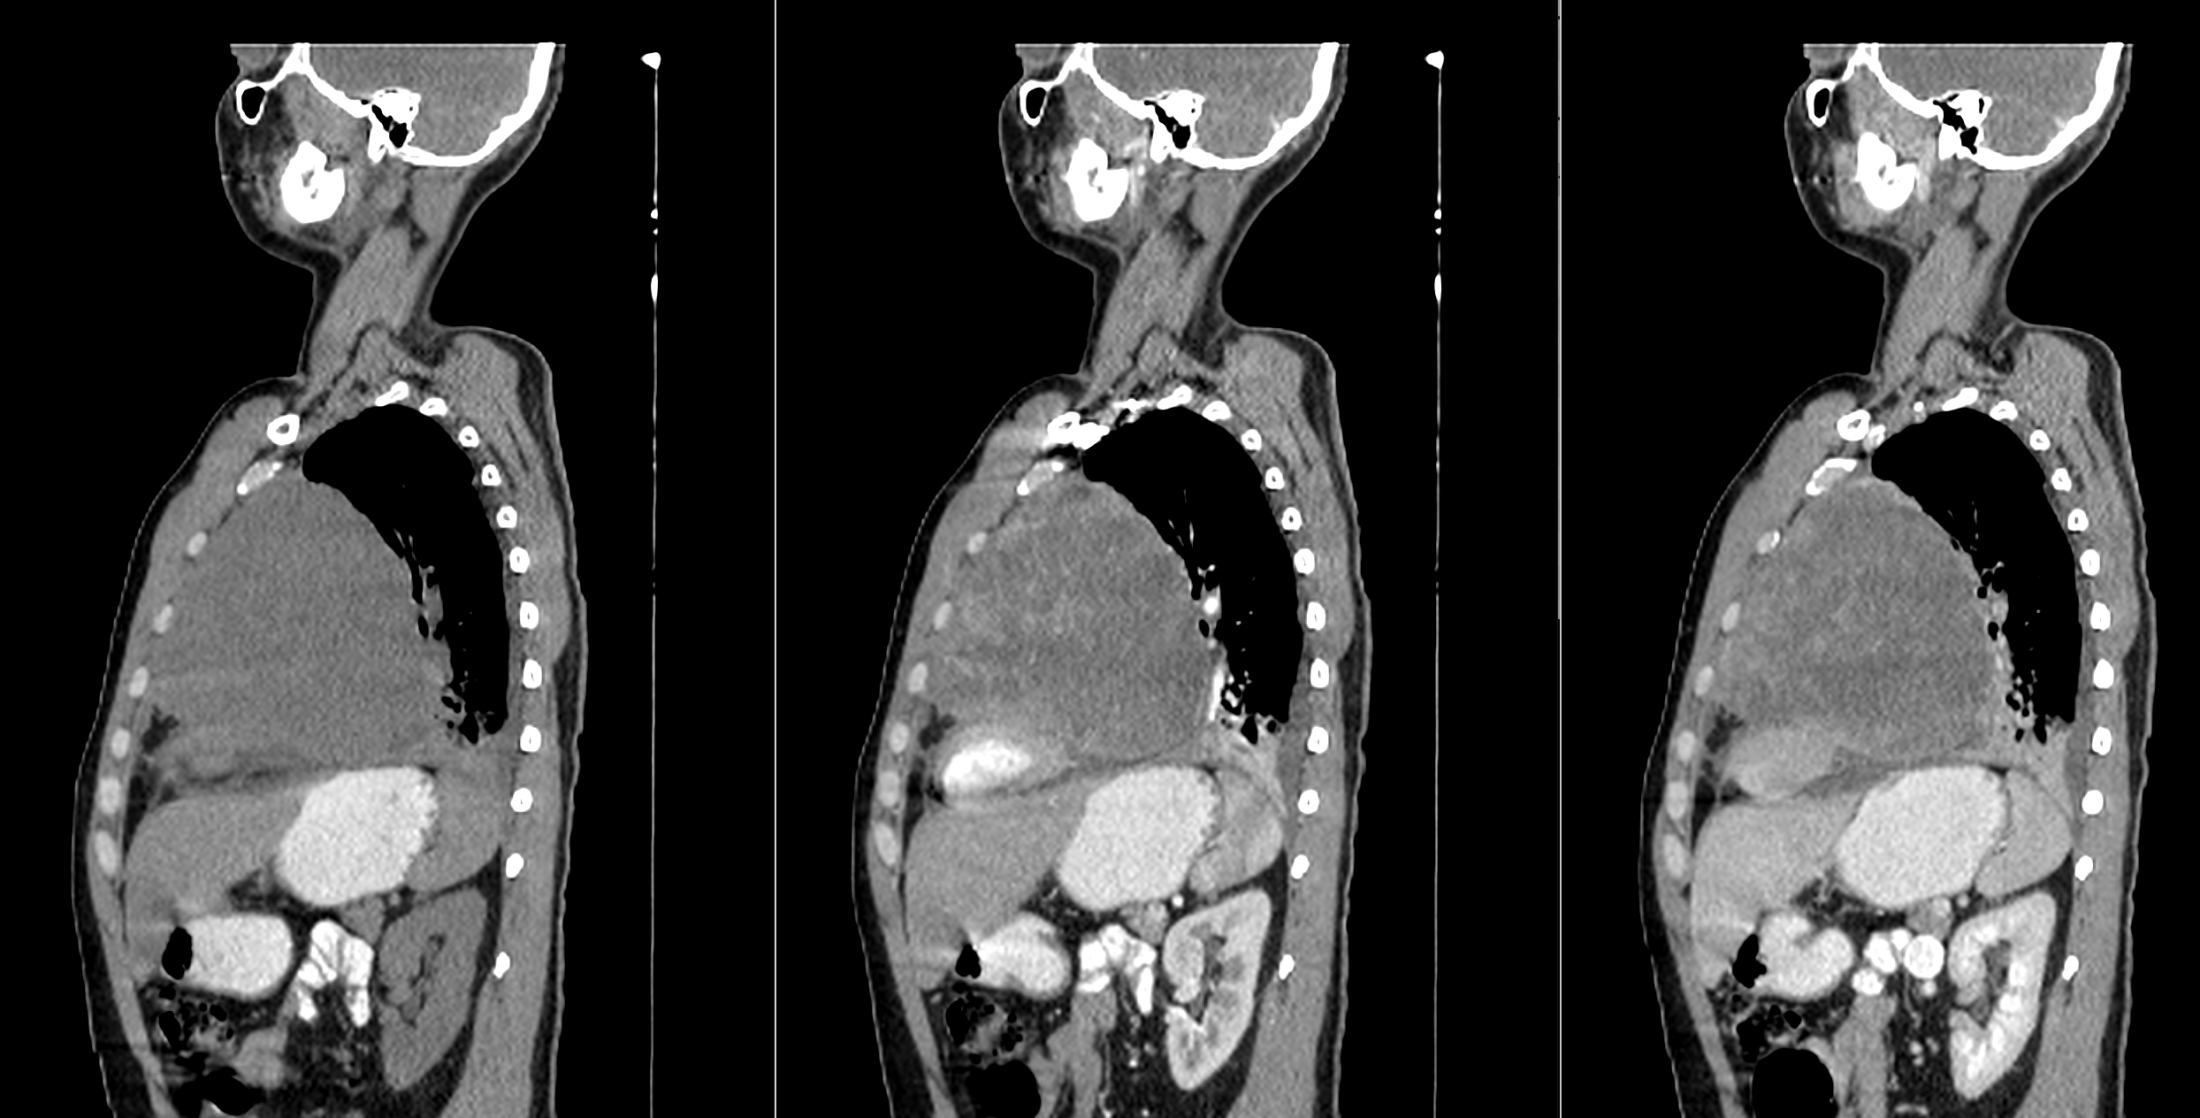

图5 矢状面成像表现与侧位片一致。

后前位胸片显示左肺周围病变,伴有对侧气管移位和心缘剪影征阴性,同时由于对侧肺代偿性过度充气导致左半膈肌升高。侧面投影显示胸骨后间隙占位,并伴“脊柱征”。增强CT显示先前识别的病变表现不均匀性,主要呈现周边强化,以及中央低密度区域,可能表明有坏死。其位于前纵隔内,不浸润邻近组织,但支气管血管结构向对侧移位。此外,可以观察到右肺动脉受压,同时存在胸腔积液